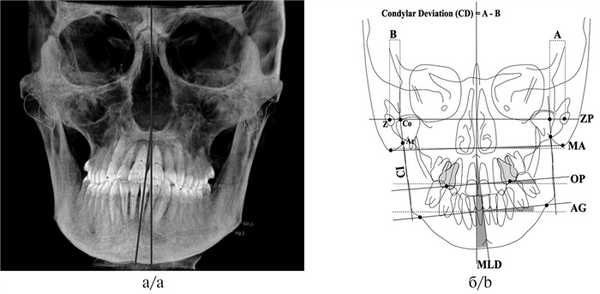

4. Оценка центральной линии. Несоответствие центральных линий челюстей возможно из-за смещения нижней челюсти в правую или левую сторону. На реформатах КЛКТ в окне цефалометрического анализа необходимо оценить показатель MLD (mandibular lateral displacement), который характеризуется образовавшимся углом между срединно-сагиттальной линией MRS, проходящей через точки Gl (Glabella — наиболее выступающая вперед в медиально-сагиттальном сечении точка на носовом отростке лобной кости, где лобная кость образует более или менее выраженную выпуклость), ANS — передняя носовая ость и Me (Menton — самая нижняя точка подбородочного симфиза — центр подбородка (рис. 3) [4].

Рис. 3. Оценка MLD нижней челюсти.

а — смещение влево [4]; б — смещение вправо.

Кроме того, необходимо обращать внимание на симметричность расположения височных ямок при ориентации черепа по срединно-небному шву в корональной проекции, так как если они находятся на разных уровнях, то клинически врач увидит наклон нижней челюсти, что может свидетельствовать о скелетной ротации сфенобазилярного синхондроза — краниальный ROLL (рис. 4).

Рис. 4. Оценка симметричности височных ямок.